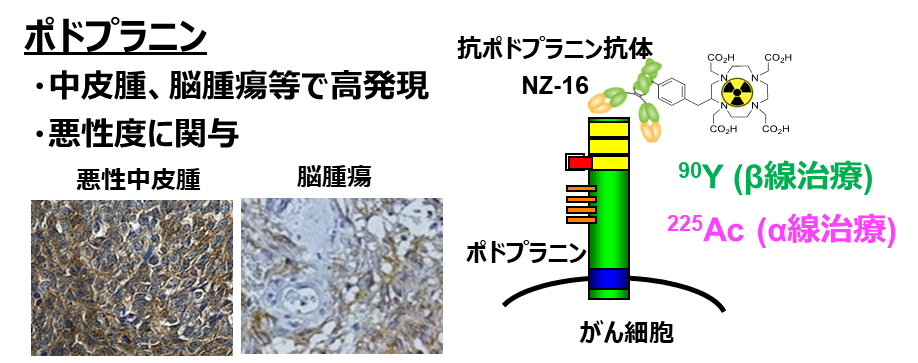

悪性中皮腫に対する新しいα線標的アイソトープ治療薬候補を開発

中皮腫細胞に結合してα線を放出する標的アイソトープ治療薬候補アクチニウム225(225Ac)標識抗ポドプラニン抗体を、中...